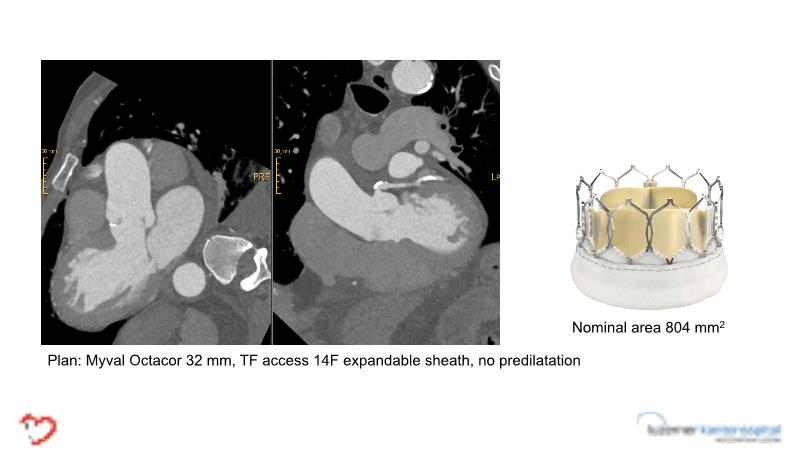

- To learn tips and tricks for managing bicuspid and valve-in-valve interventions